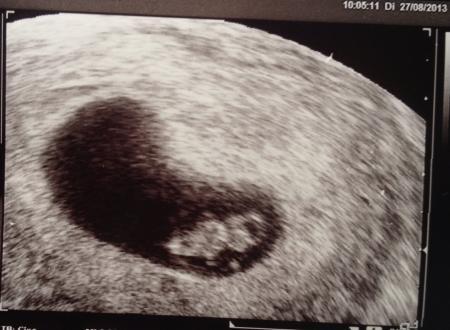

Juhuuu alles supi!!! 13 mm groß und tolles Bildchen! Daumen drücken hat geholfen ;)) ja jetzt kommt die Frage der NfM- ist halt die Frage was die Konsequenz wäre...ansonsten Brauch man die Untersuchung ja nicht machen...was meint ihr dazu??

Klar teile ich es!! :)) sooo süüß

Bild zu

-lichen Glückwunsch und weiterhin alles Gute! Süßes Bildchen!!!